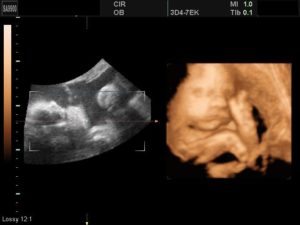

Как вариант обследования, в III триместре врач может предложить пройти не классическую допплерометрию, а 3-х мерное ультразвуковое обследование — 3D УЗИ. Такая процедура дает возможность:

- увидеть малыша в трехмерном изображении;

- сделать запись двигательной активности плода;

- точнее оценить возможность обвития пуповиной;

- в целом, качество изображения делает диагностические данные более полными и достоверными.

3D

Трехмерное УЗИ при беременности на поздних сроках дает возможность увидеть мельчайшие детали в развитии частей тела и органов ребенка. Высококачественное объемное изображение позволяет не только провести точную диагностику, но и сделать фотоснимки и видео внутриутробной жизни малыша.

С помощью 3D УЗИ возможно определить отклонения, которые порой не видны на обычном скрининге. Исследование является платным.